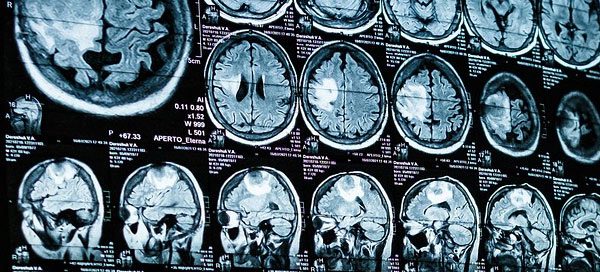

Crean un aparato portátil de resonancia magnética que facilita el diagnóstico por la imagen

La resonancia magnética (RM) es la herramienta de [...]